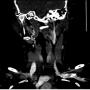

CTA showing tortuosity of right extracranial ICA at level C2 (white arrow)